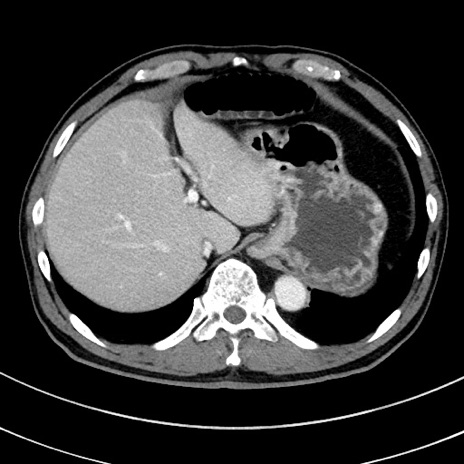

症例8(横断像)

【症例】 60歳代男性

【主訴】 黒色吐物

【現病歴】 4日前から嘔気自覚、2日前の朝食後にも嘔気あり、自分で手で嘔吐反射起こし嘔吐したところ血が混ざっていたため受診。

【既往歴】 5年前汎発性腹膜炎を伴う急性虫垂炎で手術、高血圧、前立腺肥大症、高脂血症

【身体所見】 腹部正中に手術癩痕あり 腹部平坦・軟圧痛なし膨満感あり

【データ】WBC 8400、CRP 4.54